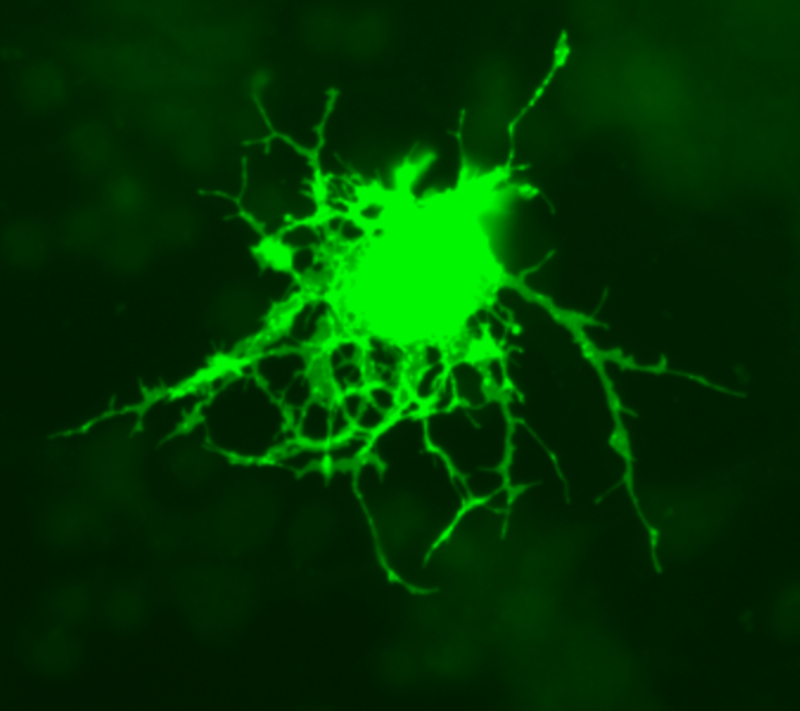

Олигодендроцит